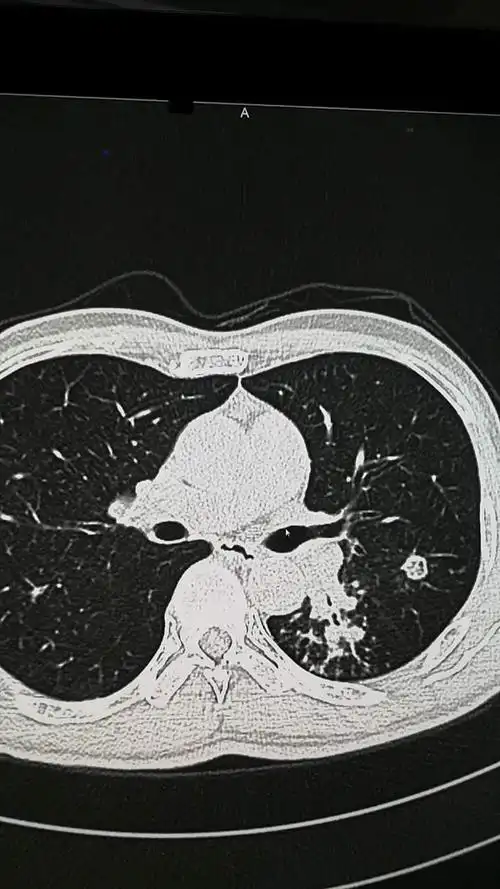

空洞型肺结核【多图】_39医疗图集-39健康网

肺结核球_肺结核结核球-万县网

伴有粘液栓的肺结核 - 美篇